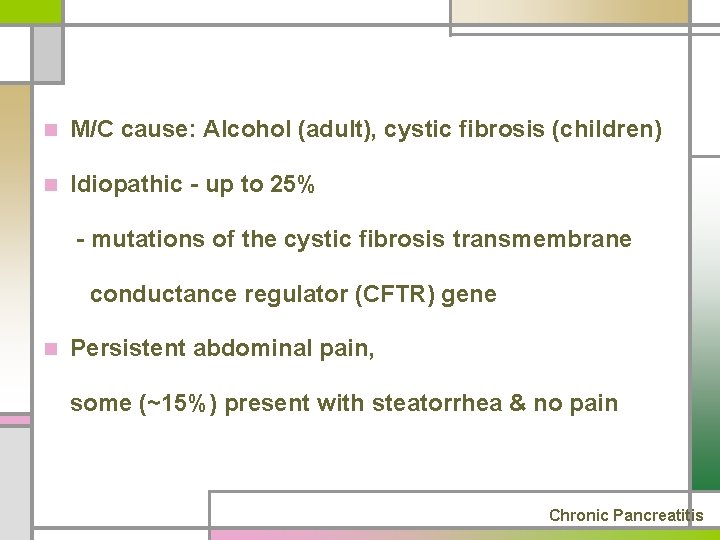

n M/C cause: Alcohol (adult), cystic fibrosis (children) n Idiopathic - up to 25% - mutations of the cystic fibrosis transmembrane conductance regulator (CFTR) gene n Persistent abdominal pain, some (~15%) present with steatorrhea & no pain Chronic Pancreatitis